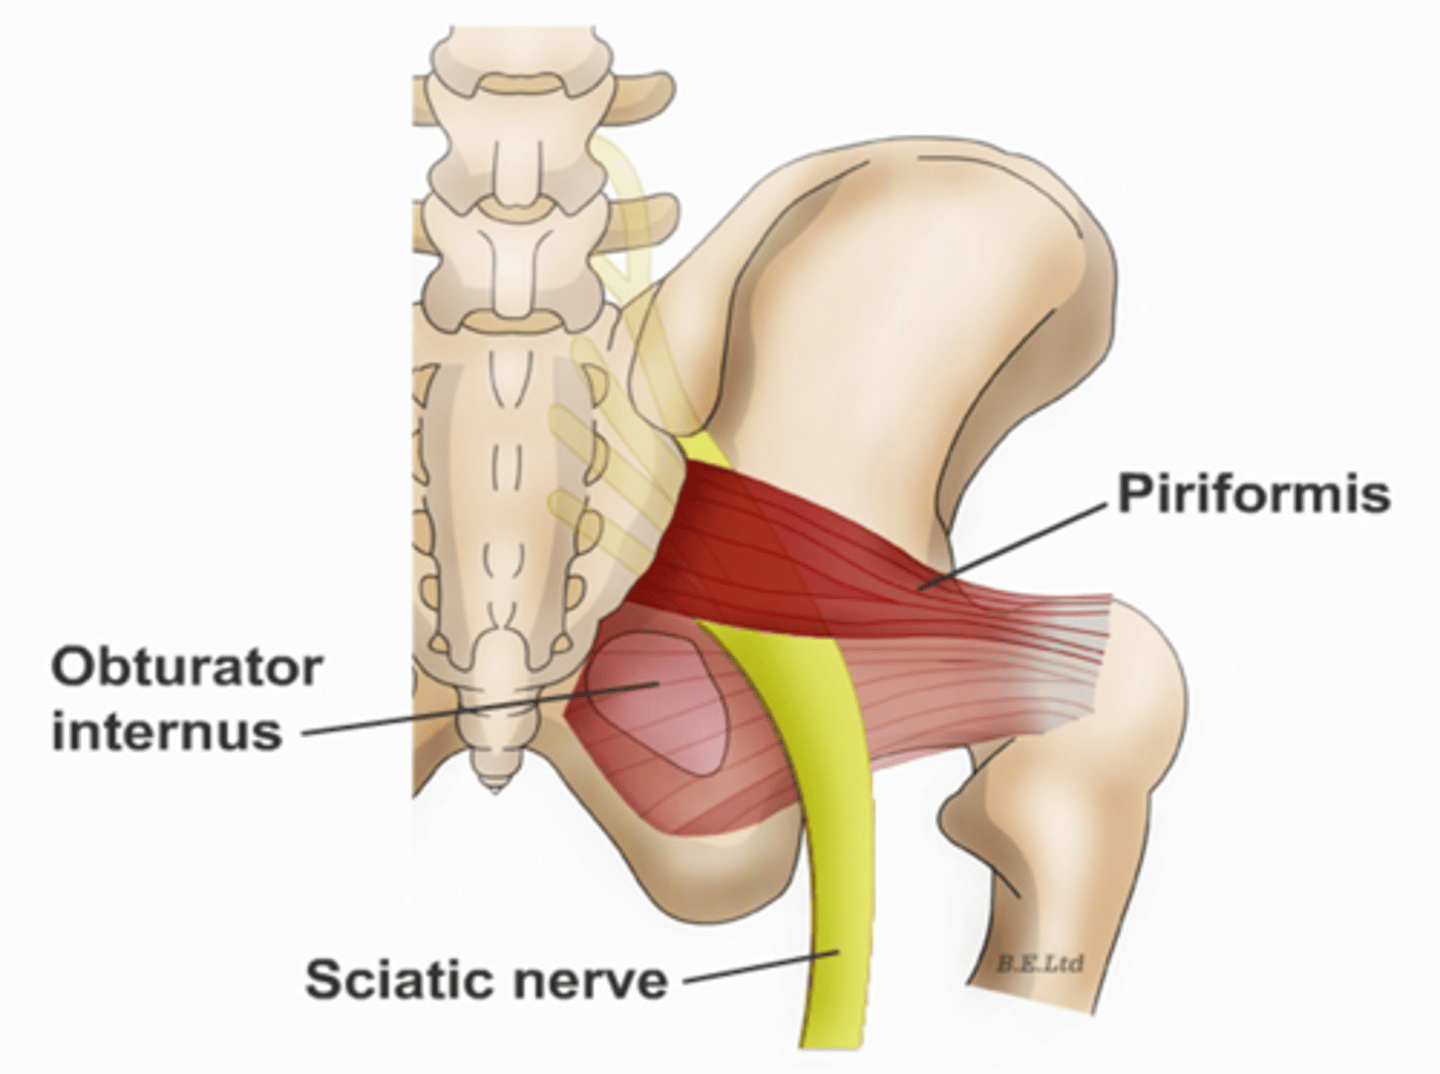

Obturator internus muscles line the ___ walls of the true pelvis

lateral

Piriformis muscles are in the ___ region of the true pelvis behind the ___

posterior; uterus

What muscle is often mistaken for ovaries?

piriformis